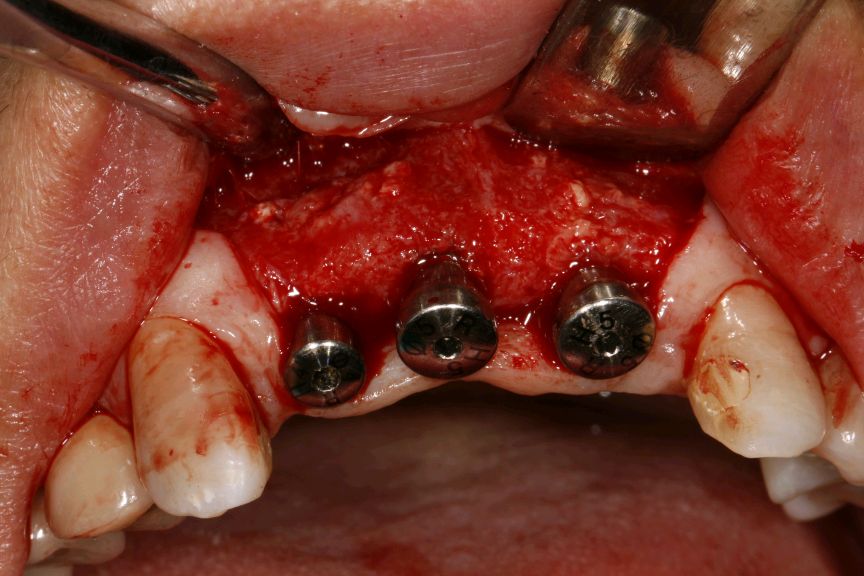

向患者交代病情、治疗计划、费用、预后等,患者知情并同意治疗。,抽静脉血20ml,12植入欧美 hiossen 种植体3.5*11.5mm,11.21植入欧美 hiossen 种植体4.0*11.5mm上覆盖螺丝,颊侧骨缺损区植入人工骨粉 傲骨0.5g及 CGF ,并盖百傲膜及 CGF 膜,严密缝和。二期三期如期进行与近日佩戴牙齿。

术中